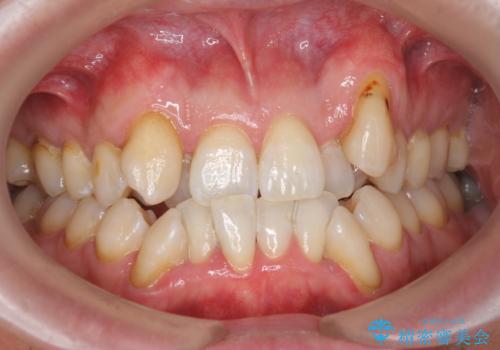

- フロスが以前よりも通りずらくなり、クリーニングしてほしいとのことでした。歯科医院でのクリーニングは3年ぶりとのことです。PMTC60分コースを行いました。

歯科医院で行なわれる専門家による徹底した歯面清掃をPMTC(Professional Mechanical Tooth Cleaning)といいます。専用の機器とフッ化物入り研磨剤を使用して、歯みがきで落とせない歯石や磨き残したプラークを中心に総ての歯面の清掃と研磨を行ない、齲蝕や歯周病になりにくい環境を整えます。

歯石が溜まると、歯と歯の間が埋め尽くされてしまい、デンタルフロスが通りずらくなったり、通せなくなります。